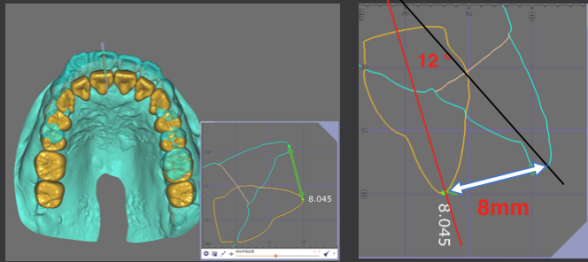

· 侧貌美学预告后,确定了上前牙矢状面前后向的位置关系,中切牙在矢状面上的位置变化:将唇倾的上前牙直立,上中切牙角度减小12度,切端内收8mm。

· 根据正侧貌美学预告,确定了咬合重建最重要的起点,上中切牙三维位置 ,𬌗面参看(FH平面)眶耳平面,并指导全口数字化排牙。